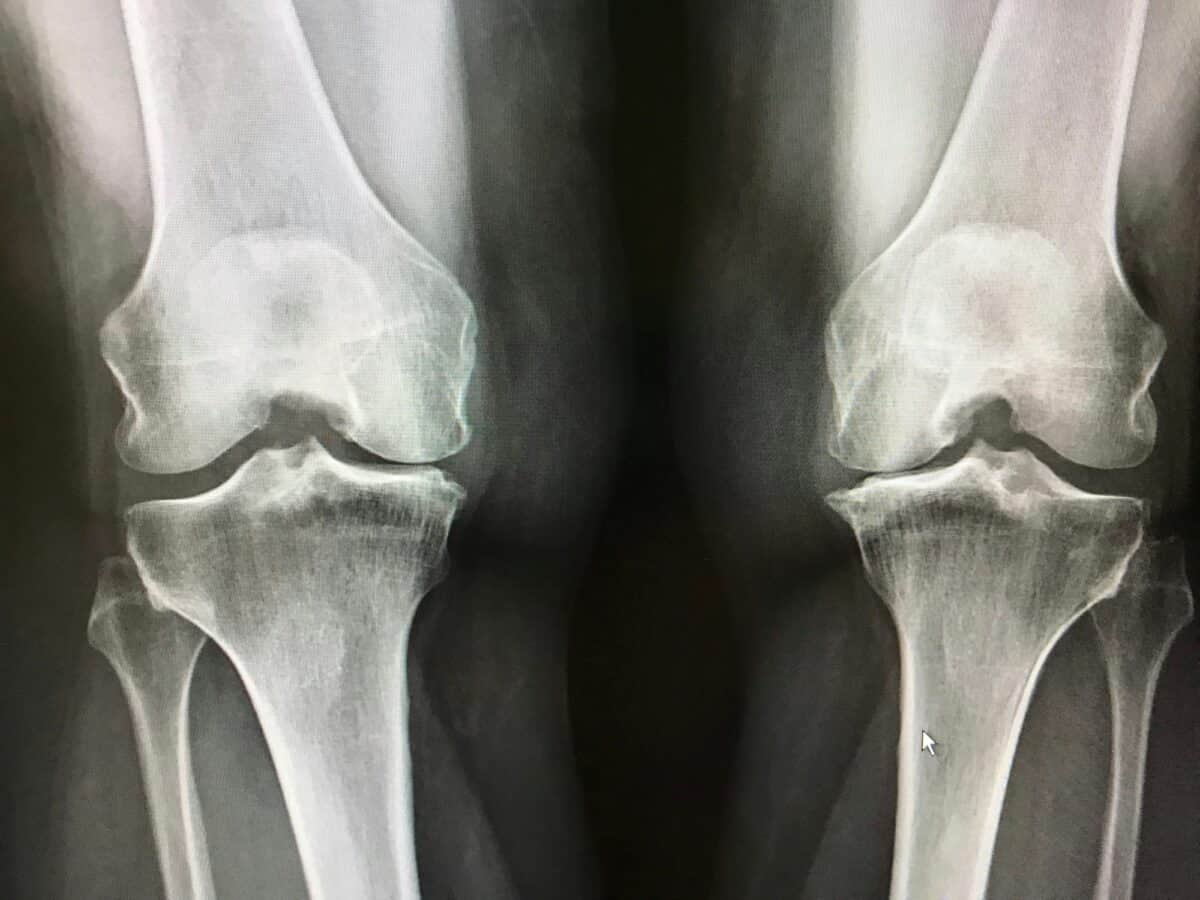

- Radiographie : C’est l’examen de référence. Elle révèle :

- Le pincement de l’interligne articulaire (espace entre les os)

- La présence d’ostéophytes (excroissances osseuses)

- La sclérose de l’os sous-chondral (densification osseuse)

- D’éventuelles géodes (petites cavités dans l’os)

- Classification radiologique : La classification de Kellgren et Lawrence, qui comporte 5 stades (de 0 à 4), est couramment utilisée pour évaluer la sévérité radiologique de l’arthrose.